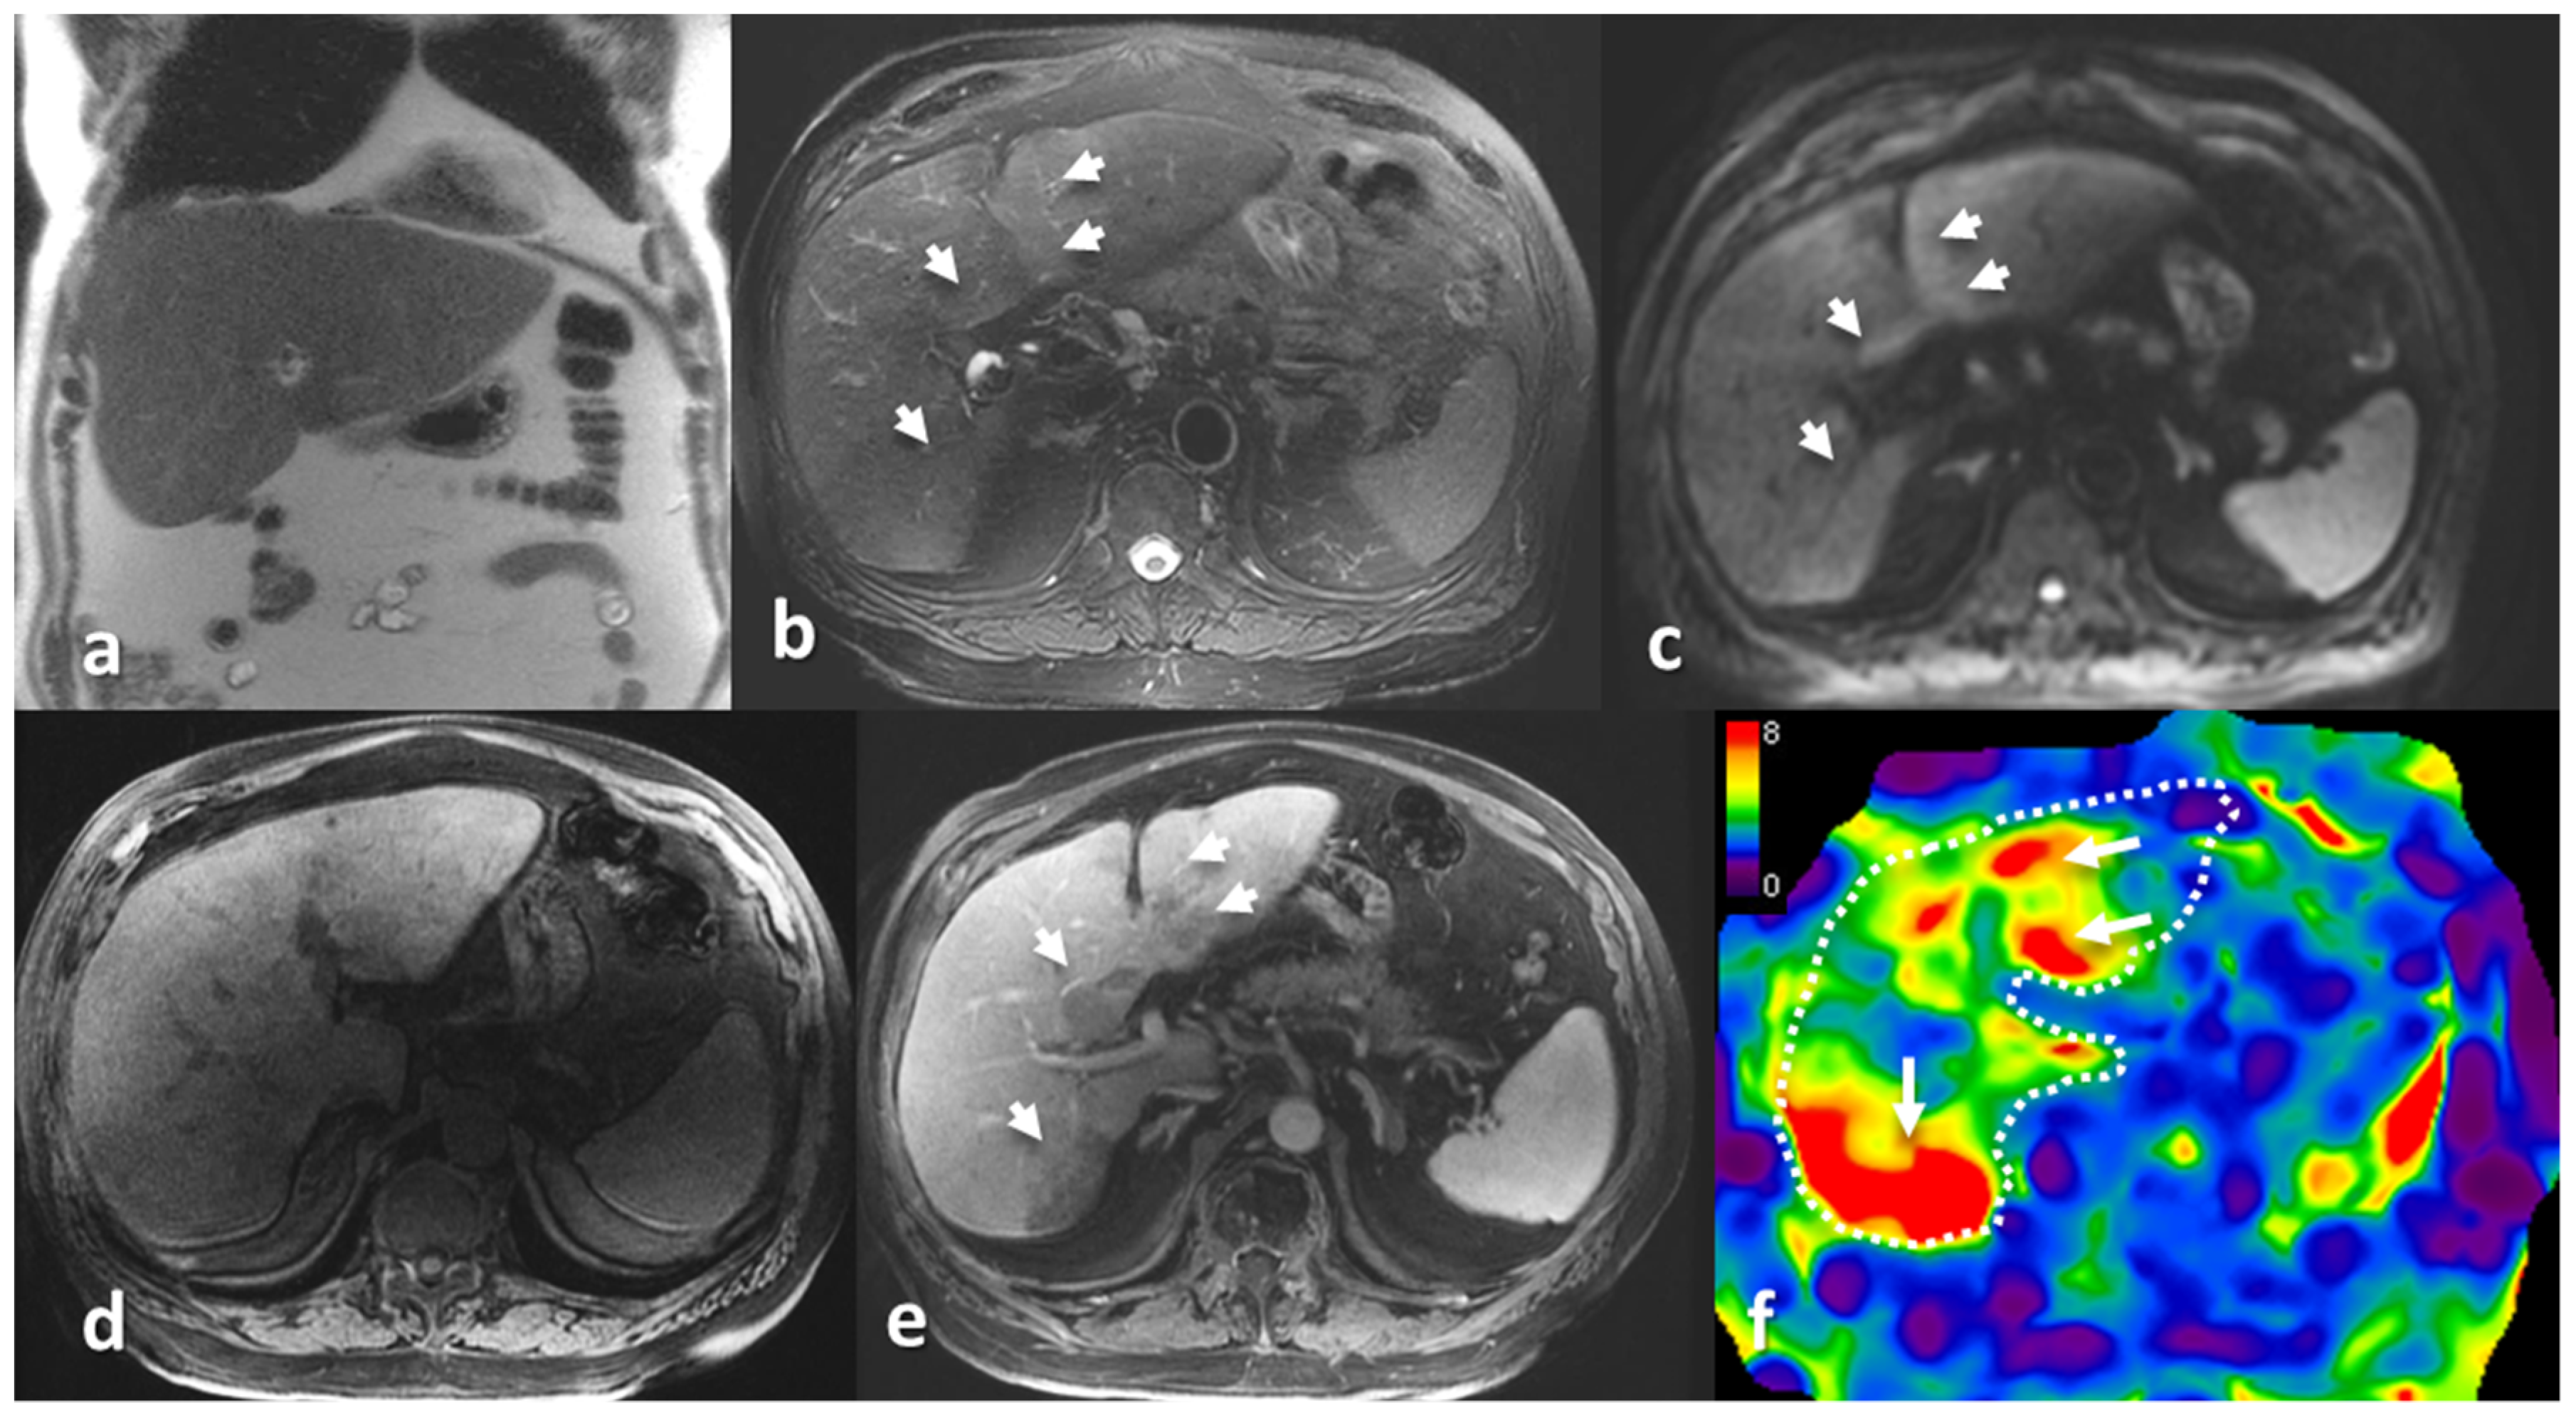

- Srinivasan, S.; Tan, Y.Q.; Teh, H.S.; Lee, P.J.; Khoo, R.N. Primary hepatic amyloidosis presenting as nodular masses on the background of diffuse infiltration and extreme liver stiffness on MR elastography. J. Gastrointestin. Liver Dis. 2014, 23, 437–440. [Google Scholar]

- Trifanov, D.S.; Dhyani, M.; Bledsoe, J.R.; Misdraji, J.; Bhan, A.K.; Chung, R.T.; Samir, A.E. Amyloidosis of the liver on shear wave elastography: Case report and review of literature. Abdom. Imaging 2015, 40, 3078–3083. [Google Scholar] [CrossRef] [PubMed]

- Matsuda, S.; Motosugi, U.; Kato, R.; Muraoka, M.; Suzuki, Y.; Sato, M.; Shindo, K.; Nakayama, Y.; Inoue, T.; Maekawa, S.; et al. Hepatic Amyloidosis with an Extremely High Stiffness Value on Magnetic Resonance Elastography. Magn. Reson. Med. Sci. 2016, 15, 251–252. [Google Scholar] [CrossRef]

- Wells, M.L.; Fenstad, E.R.; Poterucha, J.T.; Hough, D.M.; Young, P.M.; Araoz, P.A.; Ehman, R.L.; Venkatesh, S.K. Imaging Findings of Congestive Hepatopathy. Radiographics 2016, 36, 1024–1037. [Google Scholar] [CrossRef] [PubMed]